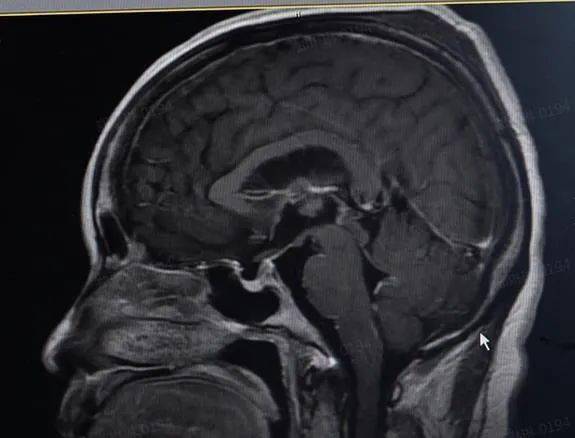

接诊医生结合患者的病史和体征 , 认为是颅内感染的可能性较大 。最终 , 在患者的脑脊液及血清中找到了李斯特菌 , 进一步证实了医生的判断 。 给予抗感染等对症治疗后 , 陈阿姨的症状逐渐好转 , 将于近日出院 。